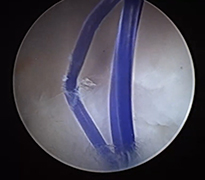

El bileği artroskopisi, el bileği ekleminin küçük kesilerden girilerek kamera ve özel cerrahi aletler yardımıyla değerlendirilmesi ve tedavi edilmesini sağlayan modern bir yöntemdir. Bu teknik sayesinde eklem içi yapılar detaylı şekilde görüntülenebilir. Özellikle bağ yaralanmaları, kıkırdak hasarları, TFCC (üçgen fibrokartilaj kompleks) lezyonları ve bazı kırık sonrası problemlerinin tanı ve tedavisinde kullanılır. Hastalar genellikle el bileğinde ağrı, hareket kısıtlılığı veya tıklama hissi ile başvurur.

Artroskopik yöntem, açık cerrahiye göre daha küçük kesilerle yapıldığı için doku hasarı daha azdır ve iyileşme süreci genellikle daha hızlıdır. İşlem sırasında hem tanı konulabilir hem de gerekli onarımlar aynı seansta gerçekleştirilebilir. Ameliyat sonrası kısa süreli istirahat ve ardından kontrollü egzersiz programı önerilir. Uygun hastalarda el bileği artroskopisi, ağrının azaltılması ve fonksiyonun geri kazanılması açısından etkili ve güvenilir bir tedavi seçeneğidir.